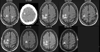

Taenia solium (the pork tapeworm) is present in most developing countries, where it is a frequent cause of seizures and other neurological disease. Parasitic larvae invade the human brain, establish, and eventually resolve, leaving a calcified scar. While these lesions are common in endemic regions, and most of these are clinically silent, a proportion of individuals with calcified cysticerci develop seizures from these lesions, and 30-65% of these cases are associated with perilesional edema (PE), likely due to host inflammation. This manuscript summarizes the importance, characteristics, natural history, and potential prevention and treatments of symptomatic calcified neurocysticercosis (NCC).